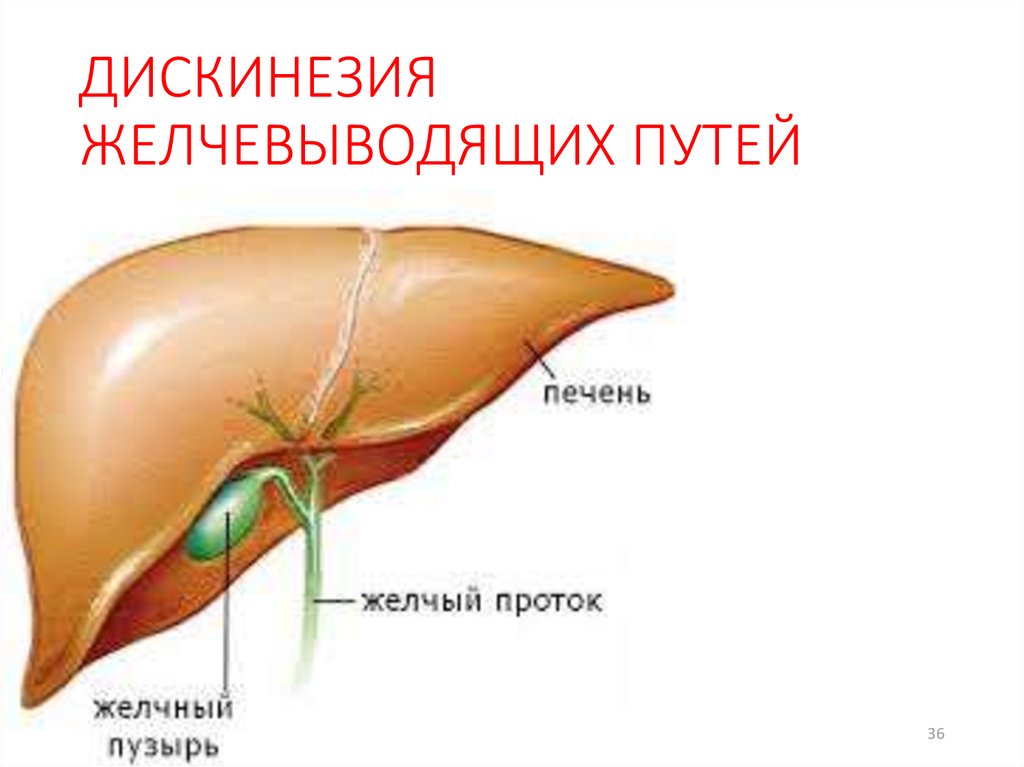

Признаки заболеваний печени: Важные симптомы и рекомендации